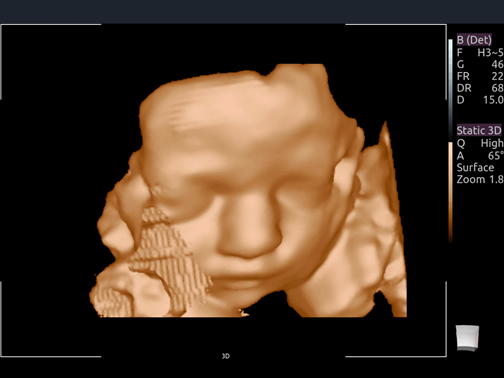

Invictus E5

O ultrassom Invictus E5 apresenta um design moderno e exclusivo, com perfeito fluxo de trabalho e interface intuitiva.

Dentre suas características inovadoras, podemos destacar a tela em LCD com rotação de 60° para ambos os lados, para otimização da visualização durante os exames; tela touch screen com menu totalmente customizável; painel de controle totalmente selado para facilitar limpeza e desinfecção da superfície, o que o torna referência para ser utilizado principalmente em Centro Cirúrgico.

Apresenta excelente qualidade de imagem, trabalho otimizado através de presets pré-determinados, sensibilidade e eficiência em aplicações de Point of Care e portanto, uma perfeita relação custo benefício.